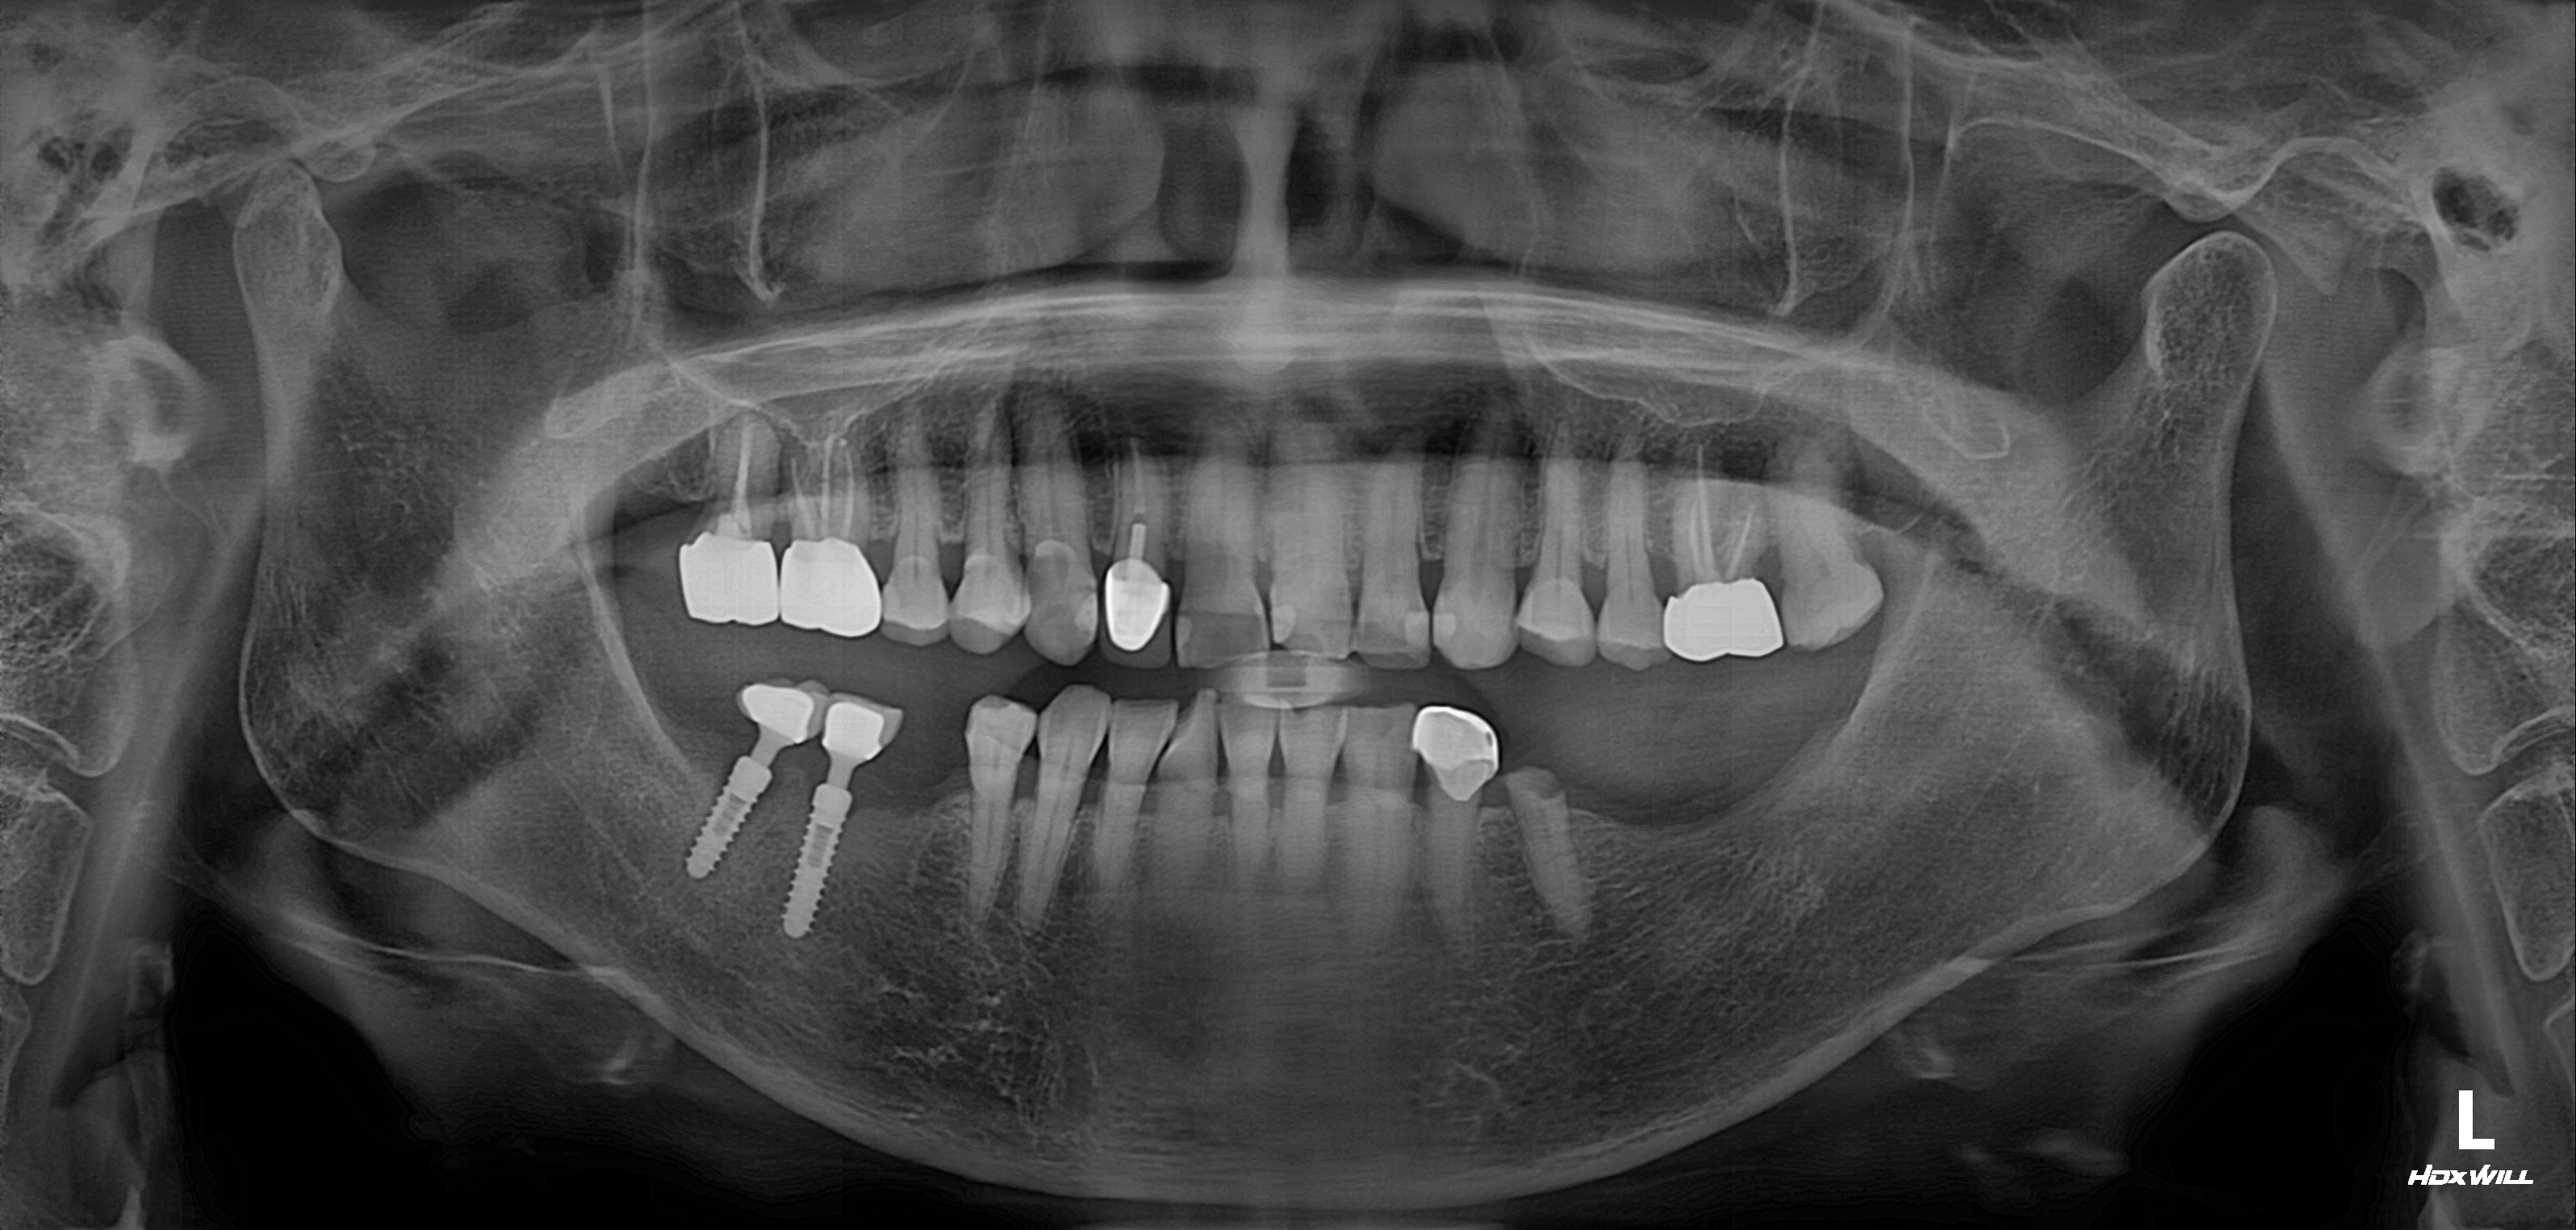

수술 전

수술 후

구치부 임플란트 식립사례

전후사진